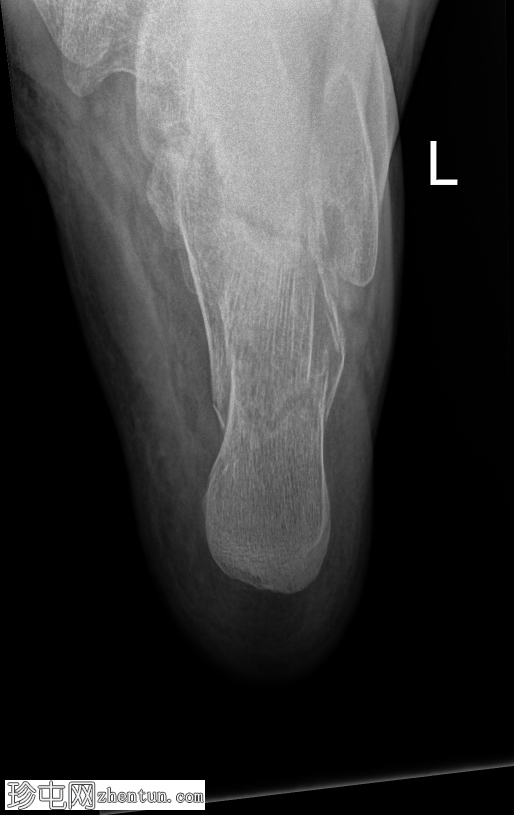

正面片

左侧跟骨关节内粉碎性骨折。骨折线贯穿跟骨体,累及并破坏距下关节后关节面,并沿跟骨外侧可见一处骨折。骨折始于距下关节中央,向下向后延伸。跟骨整体高度降低,后关节面凹陷,Böhler角变平,Böhler角明显减小,提示后关节面凹陷。

距骨、舟骨以及外踝和后踝均完整,踝穴和韧带联合完整。距下关节和跟骰关节未见脱位。软组织肿胀亦可见。

跟骨骨折是跗骨中最常见的损伤,通常由轴向负荷力引起,例如高处坠落或高强度冲击创伤。本例左侧跟骨的侧位片和轴向片显示,关节内粉碎性骨折延伸至距下关节后关节面,伴有高度降低和后关节面凹陷。

Böhler角(由跟骨前后关节面连线的交点定义)显著减小(约5-10°,正常值为20-40°)。Böhler角的减小反映了后关节面的塌陷,并提示跟骨结构性损伤严重。